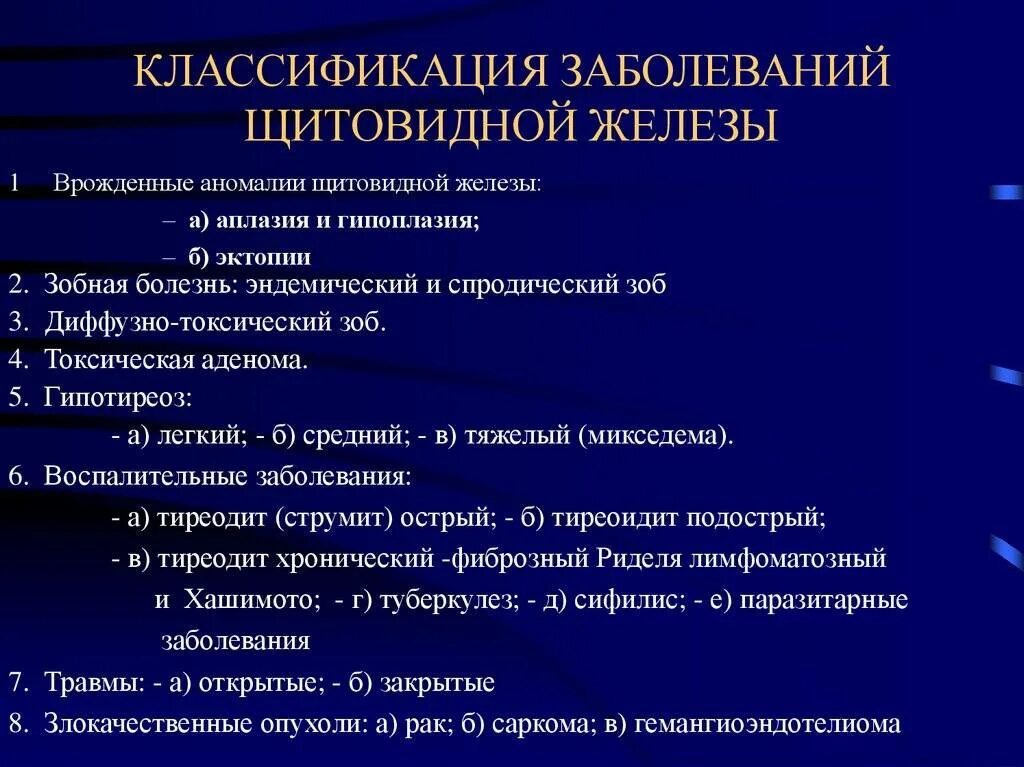

Злокачественные опухоли щитовидной железы классификация. К злокачественным новообразованиям щитовидной железы относятся:. Доброкачественные щитовидной железы классификация. Доброкачественные новообразования щитовидной железы. Классификация заболеваний щитовидной железы. Классификация хирургических заболеваний щитовидной железы. Заболевания щитовидной железы классификация этиология. 1. Классификация заболеваний щитовидной железы?.

Классификация заболеваний щитовидной железы. Классификация хирургических заболеваний щитовидной железы. Заболевания щитовидной железы классификация этиология. 1. Классификация заболеваний щитовидной железы?. Опухоль печени доброкачественная кт. Первичные злокачественные опухоли печени. Злокачественные новообразования печени кт. Первичные и Метастатические опухоли печени.